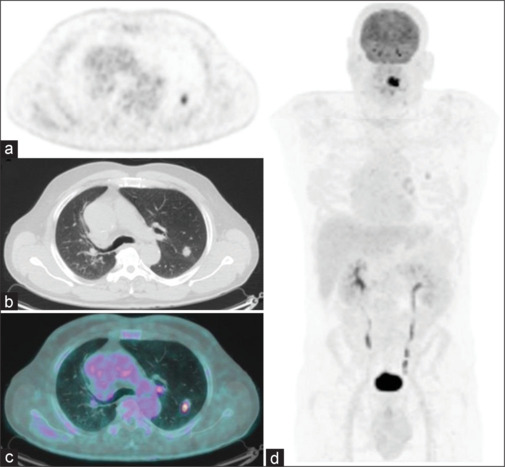

Fetal type adenocarcinoma (FTA) is a rare malignant tumor of the lung that histologically resembles an embryonic lung. Due to its rarity, no studies had investigated the possible role of the 18F-fluorodeoxyglucose positron emission tomography/computed tomography ([18F]FDG PET/CT) in the initial assessment and/or in the restaging of the disease yet. We present a case of a male patient with tongue carcinoma and incidental findings of well-differentiated FTA at [18F]FDG PET/CT. The patient was treated by specific therapy and also performed a subsequent [18F]FDG PET/CT scan that showed a significant reduction of the uptake on lung lesion. This case highlights the potential role and usefulness of PET imaging for staging and posttherapeutic restaging of well-differentiated FTA. The review of the available literature underlined the rarity of the disease since only seven reports were present. Anyway, a possible role of the [18F]FDG PET/CT in the staging of FTA is conceivable.

{"title":"[18F]FDG- PET/CT in Staging and Restaging of Fetal Type Adenocarcinoma of the Lung: A Case Report and a Review of the Literature.","authors":"Pietro Bellini, Francesco Dondi, Gian Luca Viganò, Francesco Bertagna","doi":"10.4103/ijnm.ijnm_113_24","DOIUrl":null,"url":null,"abstract":"<p><p>Fetal type adenocarcinoma (FTA) is a rare malignant tumor of the lung that histologically resembles an embryonic lung. Due to its rarity, no studies had investigated the possible role of the <sup>18</sup>F-fluorodeoxyglucose positron emission tomography/computed tomography ([<sup>18</sup>F]FDG PET/CT) in the initial assessment and/or in the restaging of the disease yet. We present a case of a male patient with tongue carcinoma and incidental findings of well-differentiated FTA at [<sup>18</sup>F]FDG PET/CT. The patient was treated by specific therapy and also performed a subsequent [<sup>18</sup>F]FDG PET/CT scan that showed a significant reduction of the uptake on lung lesion. This case highlights the potential role and usefulness of PET imaging for staging and posttherapeutic restaging of well-differentiated FTA. The review of the available literature underlined the rarity of the disease since only seven reports were present. Anyway, a possible role of the [<sup>18</sup>F]FDG PET/CT in the staging of FTA is conceivable.</p>","PeriodicalId":45830,"journal":{"name":"Indian Journal of Nuclear Medicine","volume":"39 5","pages":"376-380"},"PeriodicalIF":0.5000,"publicationDate":"2024-09-01","publicationTypes":"Journal Article","fieldsOfStudy":null,"isOpenAccess":false,"openAccessPdf":"https://www.ncbi.nlm.nih.gov/pmc/articles/PMC11884344/pdf/","citationCount":"0","resultStr":null,"platform":"Semanticscholar","paperid":null,"PeriodicalName":"Indian Journal of Nuclear Medicine","FirstCategoryId":"1085","ListUrlMain":"https://doi.org/10.4103/ijnm.ijnm_113_24","RegionNum":0,"RegionCategory":null,"ArticlePicture":[],"TitleCN":null,"AbstractTextCN":null,"PMCID":null,"EPubDate":"2025/1/25 0:00:00","PubModel":"Epub","JCR":"Q4","JCRName":"RADIOLOGY, NUCLEAR MEDICINE & MEDICAL IMAGING","Score":null,"Total":0}